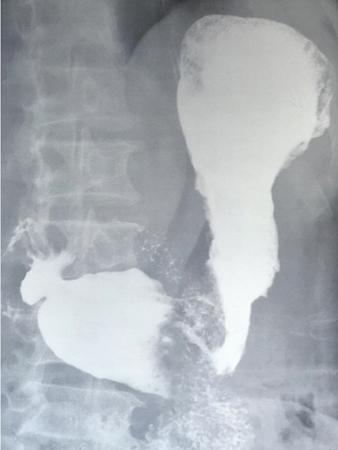

Epiphrenic diverticulum

• Pulsion diverticulum in the epiphrenic area.

• Most patients have evidence of oesophageal dysmotility.

• They tend to remain filled with barium as they lack muscle in the wall.

• May be mistaken for hiatal hernia (important to look for gastric folds).

Image

Fig. 7.4.2.4 Barium oesophagogram showing an epiphrenic diverticulum.